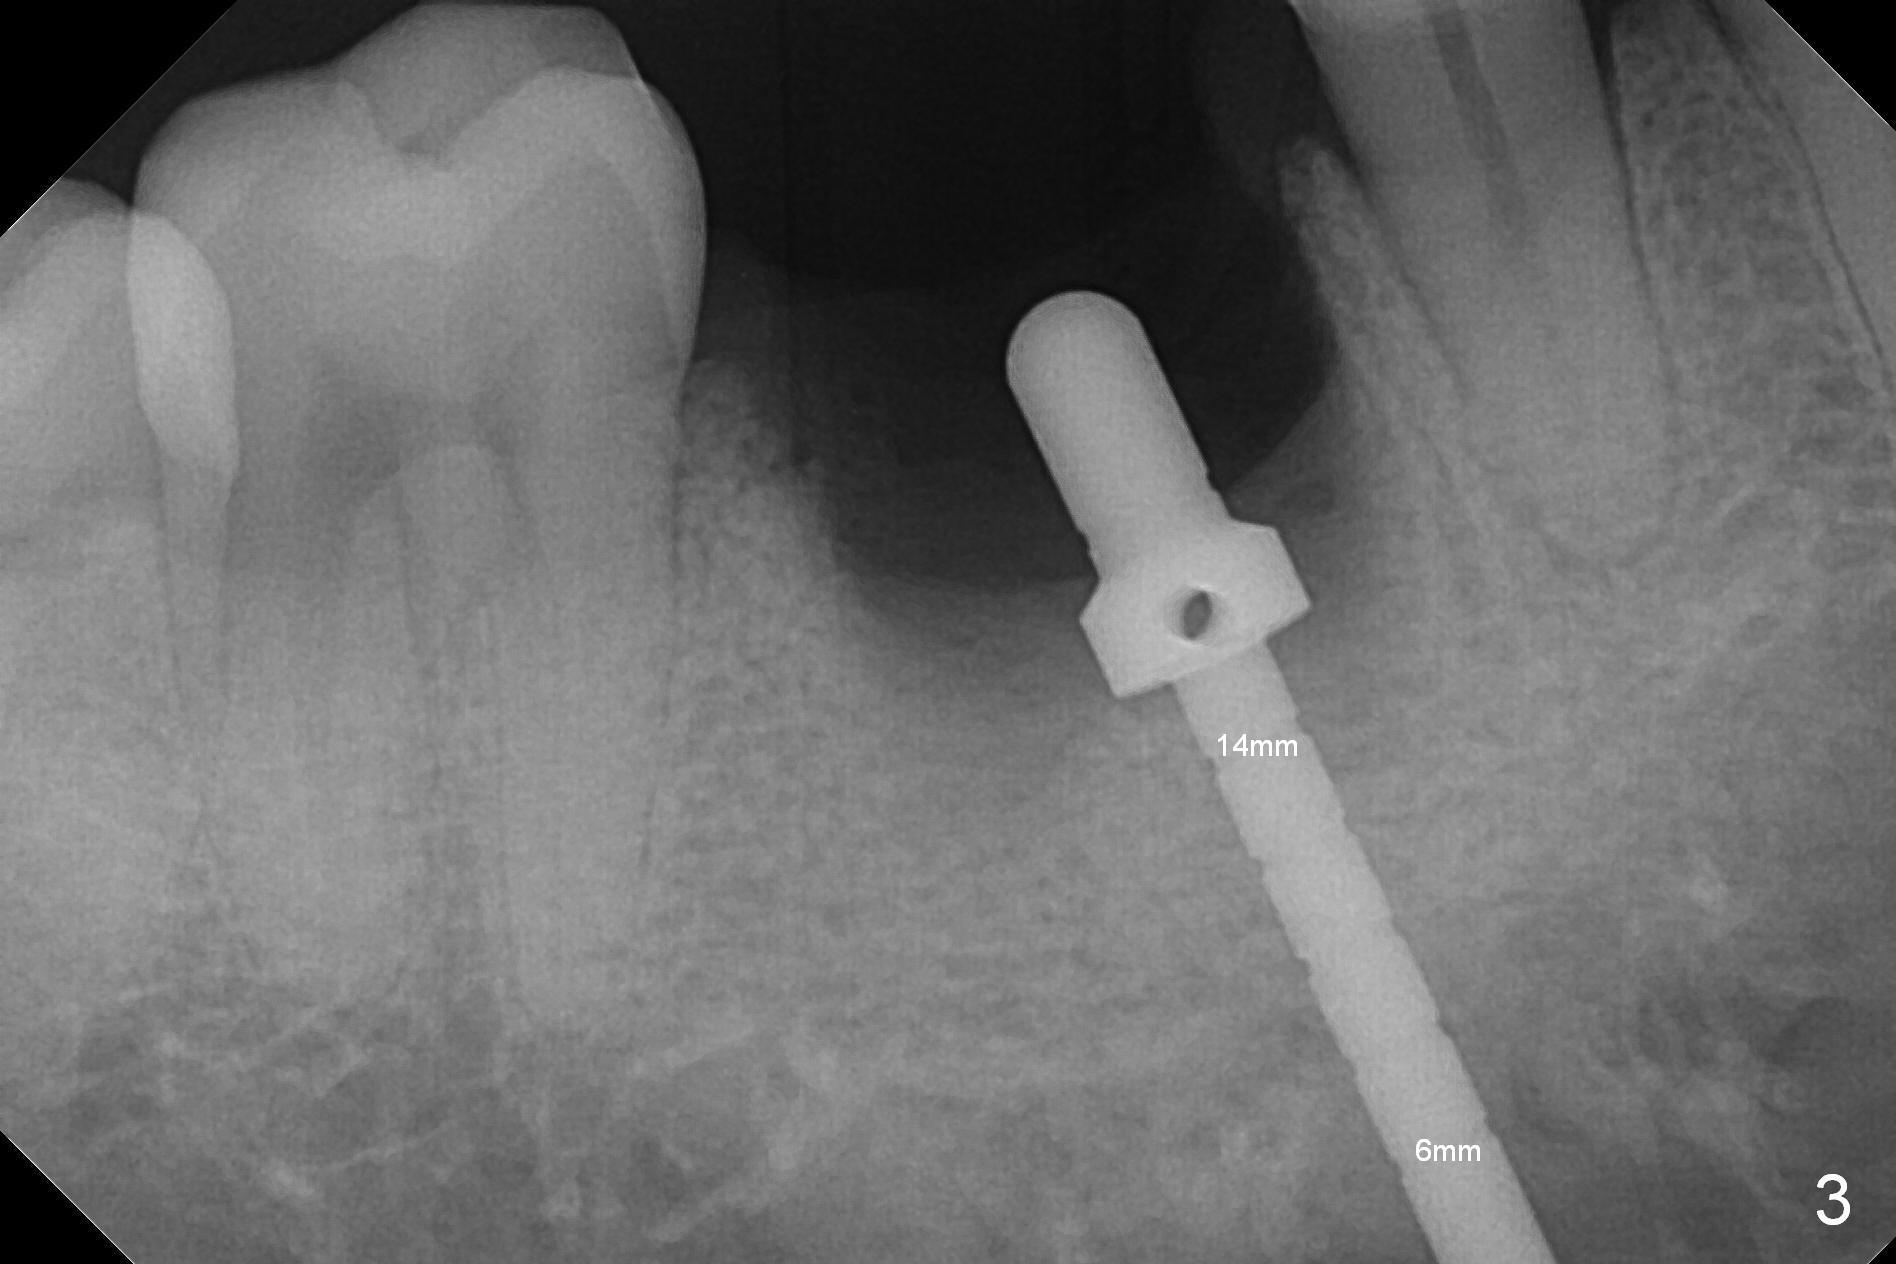

After extraction of the tooth #30 with Class V furcation involvement (Fig.1 (>),2 (L: lingual)), initial osteotomy depth is 8 mm with infiltration anesthesia, but a parallel pin is able to be inserted for 16 mm without pain (Fig.3). There is oozing from the osteotomy. Osteotomy increases in diameter with depth at 8 mm (Fig.4 (3.8 mm drill),5 (5.3 mm tap)). As the Inferior Alveolar Canal (IAC) is indistinct with increased pain during osteotomy, a 5.9x6 mm implant is placed with >50 Ncm following Septocaine infiltration (Fig.6). When bone graft (Fig.7 *) and 7.8x5.5(6) mm abutment (Fig.7,8) are placed, panoramic X-ray is taken (Fig.9). There appears to be a thick layer of spongy bone in the posterior mandible between the red and yellow dashed lines (Fig.5,9). Panoramic X-ray and/or CBCT should be taken if preop PA does not reveal IAC. This patient seems to be a bruxer. There are mandibular tori. Bone loss (furcation involvement) is not proportional to his oral hygiene status. Functional loading (progressive) should be delayed due to bruxism and the short implant.